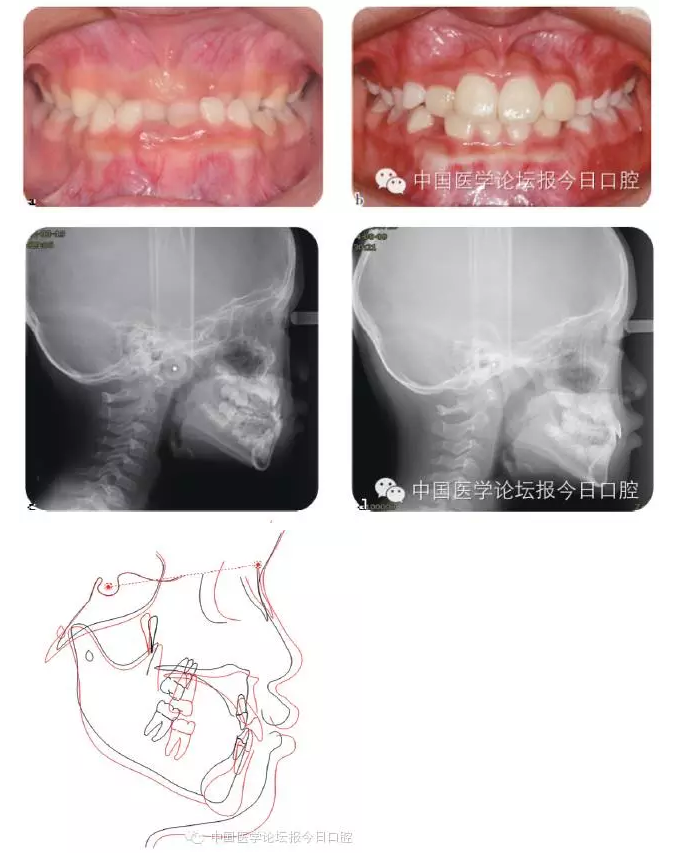

Ⅲ類骨性畸形的早期矯治

傳統(tǒng)的功能矯形概念認為應(yīng)在兒童青春發(fā)育高峰前期開始矯治。對于骨性Ⅲ類矯形治療的開始時間,國內(nèi)外一直存在爭議。

華西兒童早期矯治???,總結(jié)本科室Ⅲ類骨性矯治的療效,認為Ⅲ類骨性畸形的矯形矯治在第一恒磨牙萌出時(6歲)開始,比在青春發(fā)育高峰前期時(9歲)開始,能得到更多的骨性改變。Ⅲ類骨性畸形的早期功能矯治,見圖4。

圖4 骨性Ⅲ類錯患兒的早期矯治前、后;后續(xù)保持一直持續(xù)至兒童生長發(fā)育結(jié)束

必須強調(diào)的是,早期功能矯形治療必須保持到恒牙列初期(12歲),以維持矯形治療的效果,避免由于遺傳因素導(dǎo)致錯牙合畸形復(fù)發(fā)。